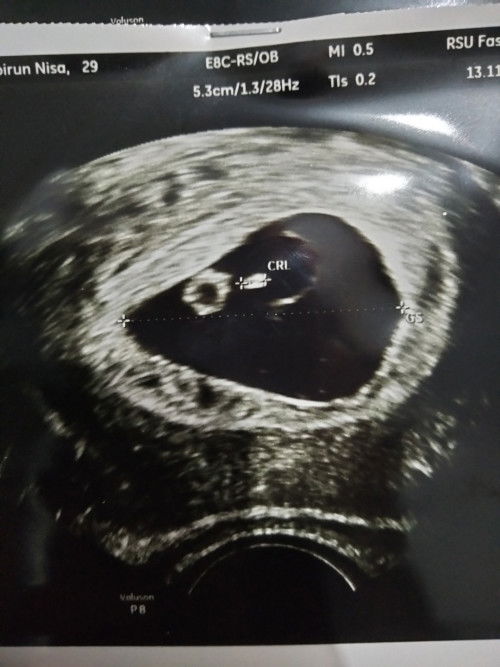

10weeks Janin tidak berkembang

Assalamualaikum bunda, 5weeks lalu usg masih kliatan kntong saja, di 10weeks ini usg perut ga kelihatan janin, sudah panik bun, dojterpun akhirnya usg trnvaginal dan disitu dokter bilang klo janin tidak berkembang, pdahal saya tidak ada flek pndrahan apapun, dokter ngerujuk untuk kuret. Kira2 masih ada harapan ga ya bun untuk keajaiban janinnya berkembang ? Apa yg harus dilakukan bund ? #bantusharing Berdasarkan foto, ada calon ari, ada air ketuban , rahim jg melonggar udah kayak bentuk alpukat menurut ukuran sudah sesuai 10weeks, tapi janin masih di 5weeks divonis tidak berkembang dan kuret. #bantusharing